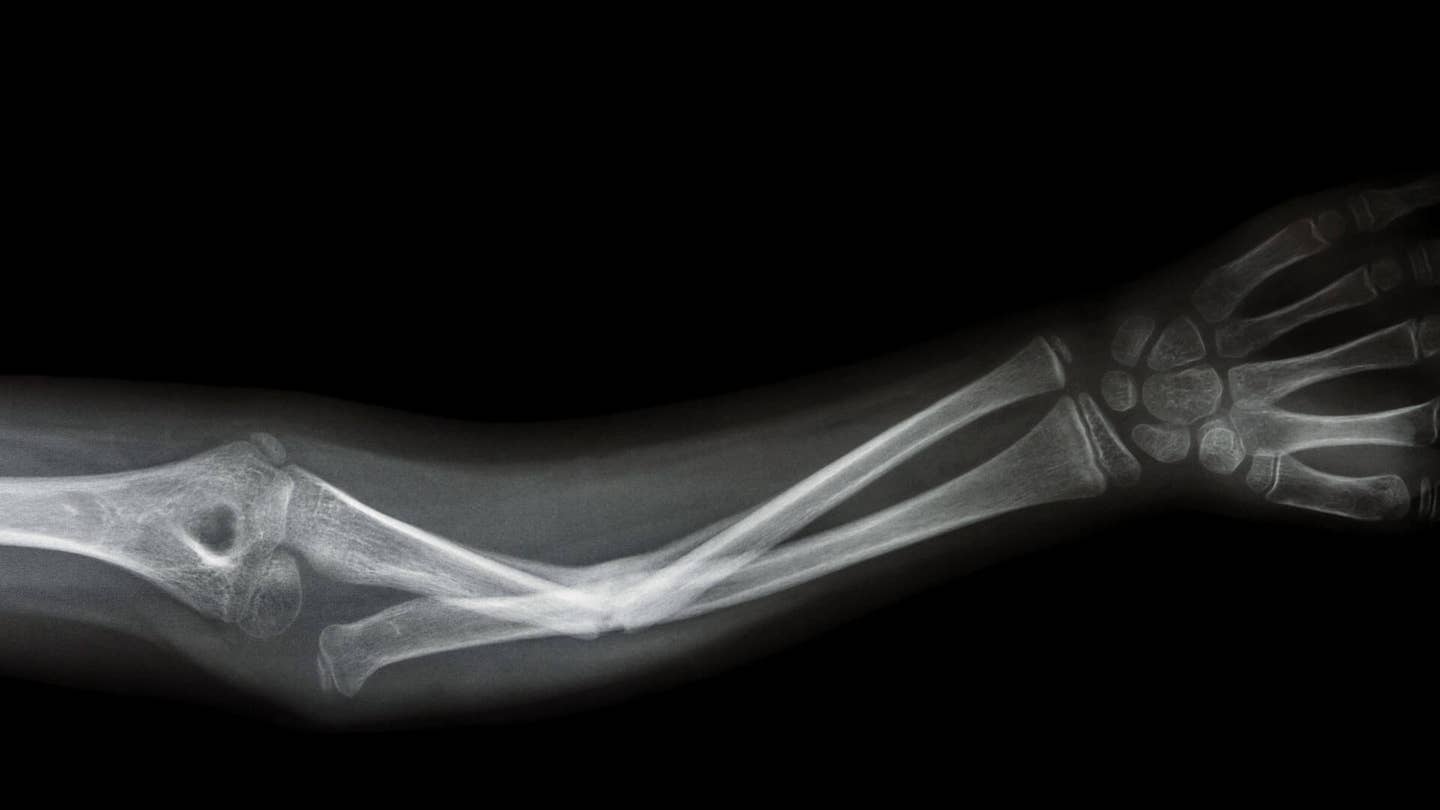

When you were a kid, did you ever sign a classmate’s cast after they broke an arm or a leg? Your name would be on display there for the rest of the semester. Broken bones are one of the worst trade-offs in childhood—a few seconds of calamity followed by months of boring rest and recovery. But children in the future may have a different story to tell as emerging tech overhauls how we fix broken bones.

The cornerstone of traditional orthopedic medicine has always been to immobilize bone breaks and allow the body to repair itself. Thankfully, our bodies do a great job repairing bones; with proper setting and enough time, bones can mend even very serious damage, turning out almost as good as new.

Modern physical therapy and recovery techniques have enhanced this “set it and forget it” approach by exploring how activity, diet, and rest can be balanced to get the best results with a broken bone. Truly traumatic injuries can require surgeries to install pins, plates, and other structures which mandate longer recovery times, more physical therapy, and quite frankly, way too much pain. There’s room for improvement overall, but especially in these most dramatic cases.